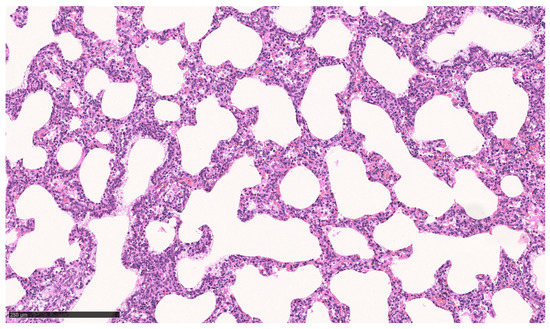

For ethical reasons, no vital born, alive pups were euthanized for microscopic tissue examination. Instead, the lungs of pups that died between 0.5 and 48 h p.n. were used for comparison (n = 3). All of these neonates suffered from respiratory problems (neonatal respiratory distress syndrome, NRDS) from the beginning of the postnatal period. A histopathologic examination of their lungs revealed either low-grade ventilated or largely nonventilated (atelectatic) lung tissue except for bronchioles and bronchi. In some localizations, aspirated squames or other amniotic fluid components (e.g., meconium) were found, as well as exfoliated pneumocytes in terminal sacculi and bronchioles (Figure 6). However, some areas of the pulmonary tissue showed moderately aerated lung saccules and dilated bronchioles (Figure 7).

Figure 7. Lung, dorsal lobe of vital pup after death 48 h p.n. Lung saccules and bronchioles are moderately dilated; Bar: 250 µm.